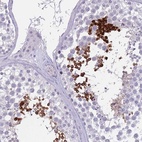

Immunohistochemistry analysis in human testis and endometrium tissues using Anti-SUN5 antibody. Corresponding SUN5 RNA-seq data are presented for the same tissues.